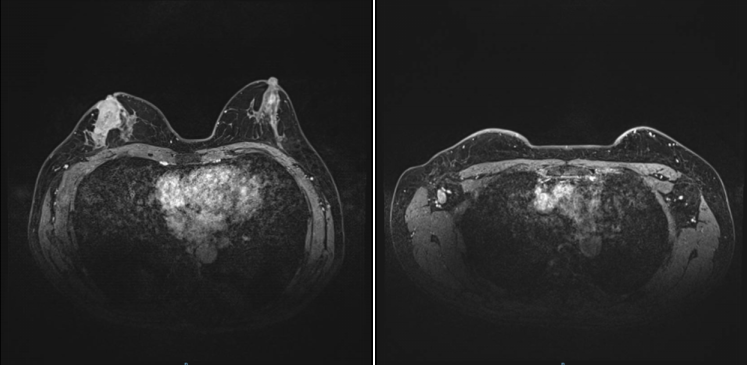

2021-12-01,乳腺MR:右乳外上象限腺体内(约9-12点钟方向,前中带区)见一异常信号肿块影,大小约3.9×2.7cm,符合乳腺癌表现(BI-RADS 6类),侵及邻近皮肤及乳头。右侧腋窝数个增大及稍大淋巴结,较大者大小约为2.1×1.3cm,考虑转移。

图2.乳腺MR(2021-12-01)

2022-4-19,乳腺MR:右乳外上象限腺体内(约9-12点钟方向,前中带区)条片影,大小约2.5×0.7cm,较前明显缩小、强化减低。右侧腋窝数个小淋巴结,较大者短径约0.5cm,较前缩小。

图5.乳腺MR(2022-4-19)